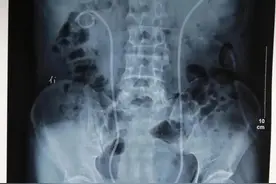

李荟,战略支援部队特色医学中心(原306医院),泌尿外科医学科普中心 刘燕/崔彦 编辑双J管,全名输尿管支架管,又名DJ管、双猪尾巴管,是两头成“J”型的空心管道,两头弯曲,中间平直,全长有多个侧孔。双J管质地非常柔软,其放入输尿管后,最终上端端卷曲在肾盂,下端卷曲在膀胱内。